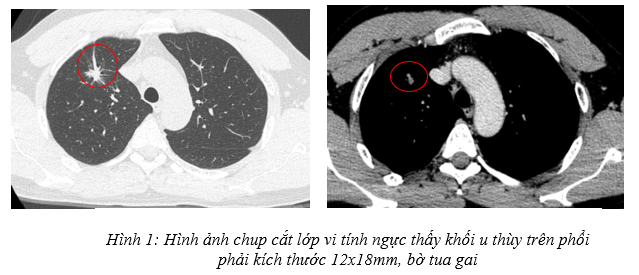

Bệnh sử: Bệnh diễn biến trước vào viện 1 tuần, bệnh nhân tự sờ thấy hạch thượng đòn trái, không đau, không sốt, không nôn, không ho, không khó thở. Bệnh nhân đi khám được chụp cắt lớp vi tính ngực phát hiện u thùy trên phổi phải kích thước 12x18mm. Bệnh nhân được nhập viện Trung tâm Y học hạt nhân và Ung bướu – Bệnh viện Bạch Mai.

– Chụp cắt lớp vi tính ngực: Thùy trên phổi phải có nốt đặc kích thước 12x18mm, ngấm thuốc cản quang, bờ tua gai, có giãn phế nang kèm dải xẹp lân cận. Thùy trên có vài nốt nhỏ dưới màng phổi đường kính 3mm.

– PET/CT: thùy trên phổi phải có nốt tốn thương tỷ trọng tổ chức, kích thước ~ 18 x 14mm, SUVmax 4,61. Hạch thượng đòn trái kích thước 14mm, SUVmax 13,08